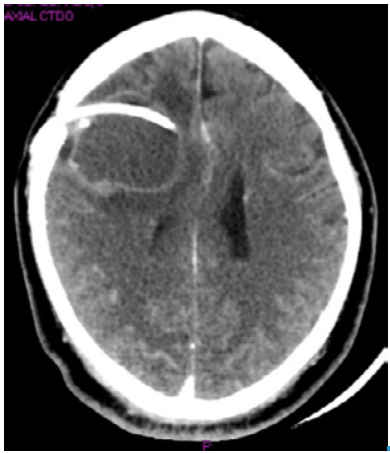

A week after admission, the patient presented with left hemiplegia and sialorrhea, and he did not have any verbal response. A craniotomy was performed to remove the cyst and conduct a histopathological study, while a ventriculoperitoneal shunt was arranged to reduce intracranial pressure (Figure 2). Macroscopically, neurosurgery reported a frontal cyst of greenish content with walls strongly adhered to the parenchyma and the frontal horn of the lateral ventricle. Histopathological analysis confirmed the suspicion of NCC and reported reactive gliosis. The patient evolved satisfactorily, did not present any type of sequelae and was discharged.

Computed tomography with right frontal subcortical cystic lesion, midline shift and ventriculoperitoneal shunt.

Figure 2: Computed tomography with right frontal subcortical cystic lesion, midline shift and ventriculoperitoneal shunt.

Source: Own elaboration based on the data obtained in the study.